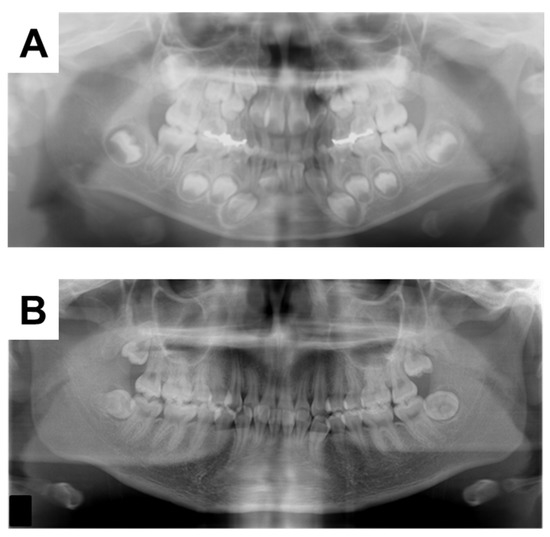

2. Case Presentation